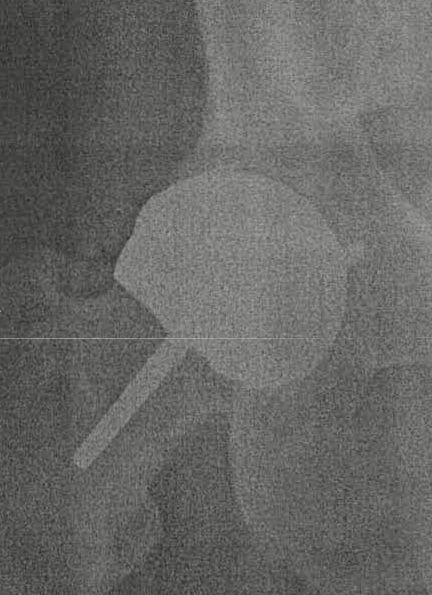

At the beginning of March 2025, I experienced what seemed like a kidney stone due to centralized pain in the lower back and abdomen. After a visit with my doctor and a blood test for cobalt, I realized that I was undergoing a metallosis event from my 2 Wright CONSERVE® Femoral Resurfacing, which are made from chrome/cobalt. My hips were resurfaced in 2006 and 2010, and I have been extremely happy with the results, which allowed me to continue my love for backpacking. I did experience a metallosis event back in 2016 when I took up playing my beloved game of handball. I quickly realized that the lateral movement of this court game was causing metal fatigue in my hips, confirmed by a high concentration of chrome/cobalt in my blood. When I realized the similarity of symptoms with this latest event, my “A-ha” moment pointed directly at the amount of skiing I had done this winter. I didn’t equate lateral movement with skiing; however, after thinking about the stress put on my hips from skiing, I knew what I had done.

The severe pain began to subside and I was able to walk the dog again, I was daily monitoring the muscle cramping and weakness of the muscles around my hips. The slow but steady progress through March was encouraging and now I am able to walk 18 holes of golf at least once a week in April. I have an appointment with a Orthopedic Surgeon in May when I hope to get more deliberate about a maintenance program for monitoring the metal fatigue. (Update)I met with my Orthopedic Doctor to discuss my MRI of my hips and all looks good. No reason to be concerned so now I can exercise without fear of doing more damage. Overall, it appears that I will be able to manage this problem and continue my plans for a return to Backpacking.